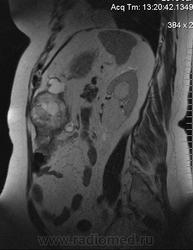

очень характерная картина для метастаза рака яичника, к сожалению.

Не могу достоверно определить локализацию метастаза брюшной полости, вероятно в лимф. узел с инвазией оободочной кишки. Рецидив С-r левого яичника думаю, что с инфильтацией левой стенки прямой кишки и культи влагалища, вторичная лимфаденопатия л/у малого таза. каликопиелоуретероэктазия (инвазия нижних отделов левого мочеточника?) Холедох широковат, но желтухи по внешнему виду нет.

Прорастание левого мочеточника рецидивной опухолью есть 100%, метастаз в большой сальник характерен для рака яичников, как и сигнальные характеристики его. Культя в данном случае шейки матки.